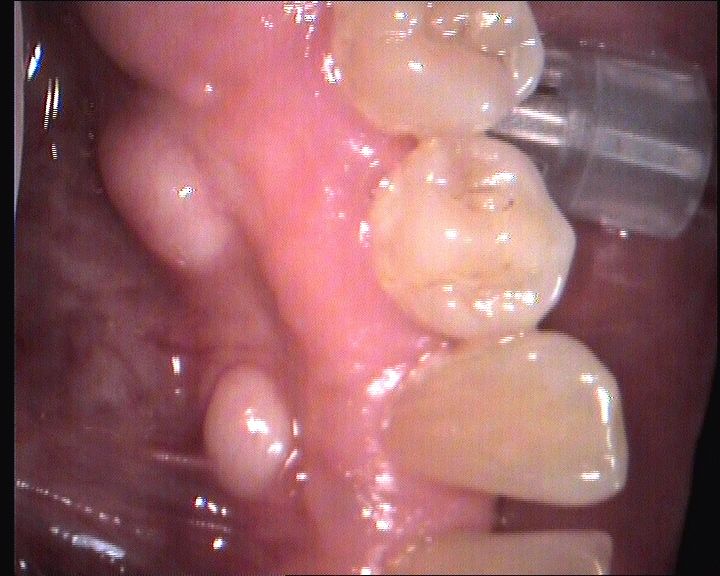

Vorrei qui presentare le fotografie di alcuni casi di stomatologia che con frequenza si riscontrano nella pratica quotidiana. Sono patologie che devono sempre essere guardate con attenzione come per esempio l’ulcera del fianco della lingua. Spesso questa è dovuta ad una otturazione incongrua o ad un altro traumatismo, rimosso il quale si risolve anche l’ulcera linguale.

Occorre, però, essere vigilanti e seguire il caso possibilmente con l’aiuto di fotografie. Infatti se rimossa la causa ipotetica, non si ha anche la scomparsa dell’ulcera entro un tempo massimo di due settimane, allora occorre fare una biopsia o meglio ancora inviare il paziente ad un centro ospedaliero di chirurgia maxillo-facciale.

Così come è opportuno riconoscere un herpes del palato rispetto ad un traumatismo da anestetico o una glossite romboidale rispetto alla quale non si può fare e non serve fare molto se non controllare le fasi infette acute.

L’esame del cavo orale non dovrebbe mai limitarsi solo all’esame dei denti, ma dovrebbe sempre primariamente e principalmente rivolgersi ai tessuti duri e molli. Solo in un secondo momento ci si dovrebbe concentrare sui denti, cioè solo dopo aver escluso patologie orali più importanti.